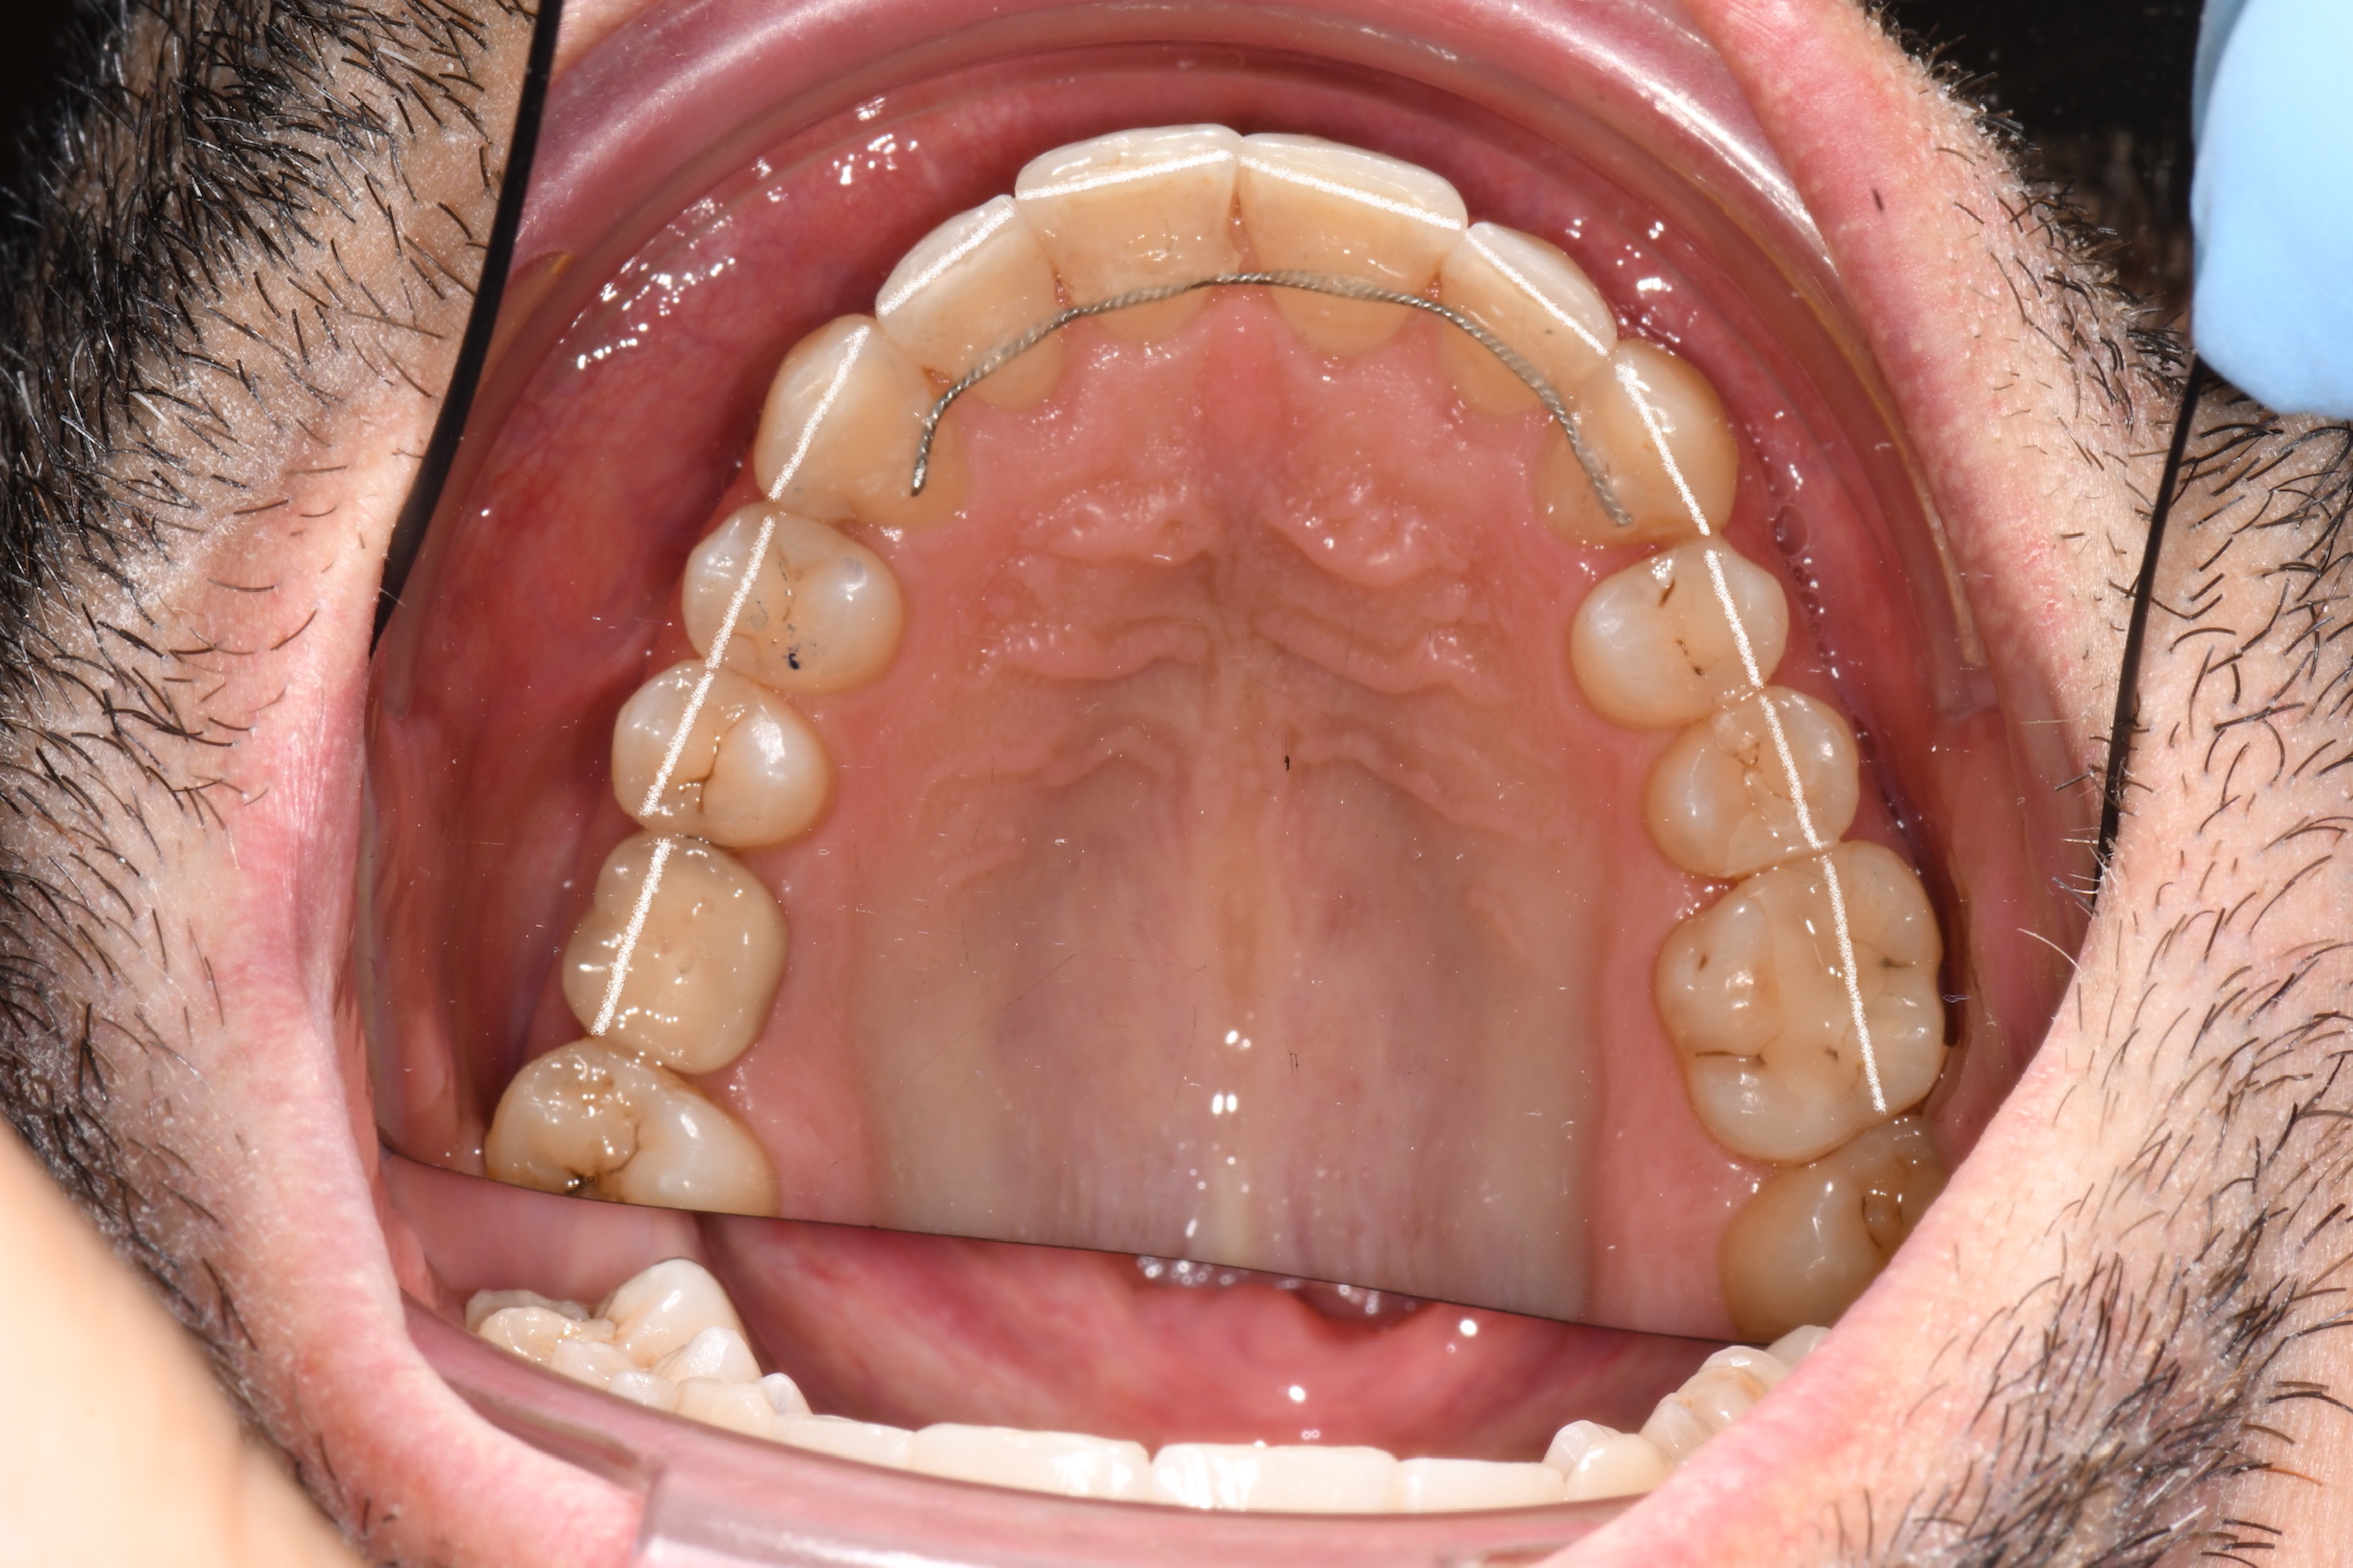

Az elmúlt évekből rengeteg szakmai referenciát tudnánk bemutatni, amelyek különböző fogszabályozási problémákat oldottak meg. Válogatva a több száz esetből, ezen az oldalon olyan képeket, információkat igyekeztünk bemutatni, amelyeknek a segítségével a jövőbeni pácienseinknek azt tudjuk üzenni: A Te fogsorod is lehet gyönyörű!

(Képeket a Pácienseink külön írásos beleegyezésével mutatjuk be!)